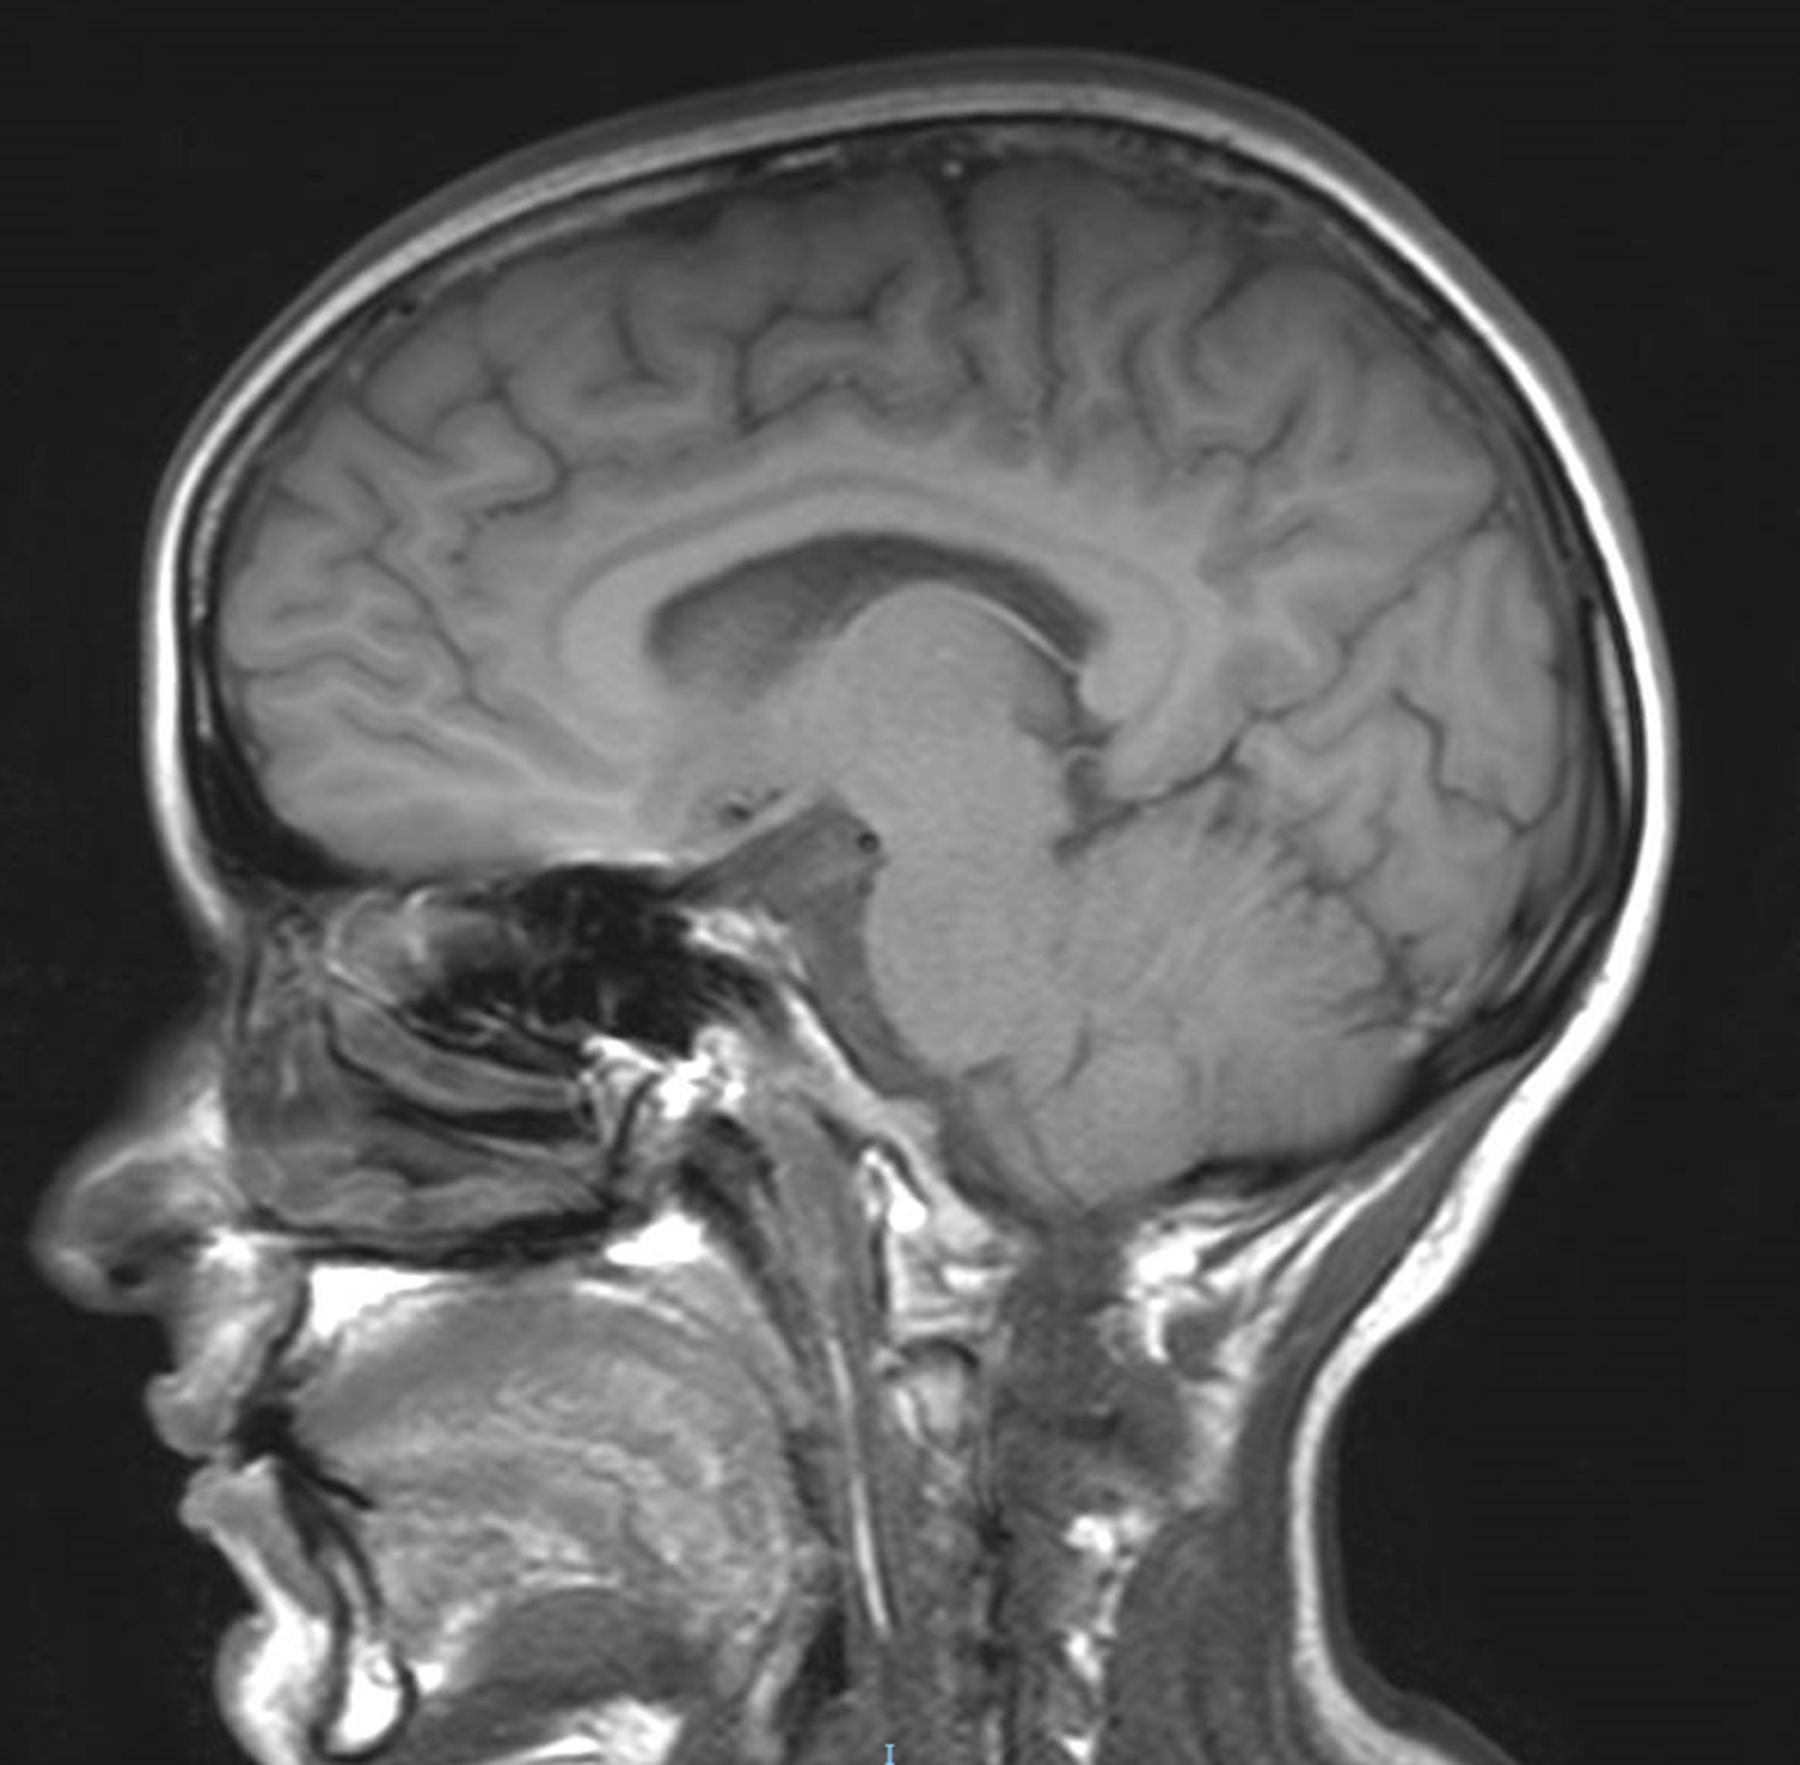

He was great: Dr. Leung has been amazing. He spent so much more time with me than any other doctor, but also much more time than I would have assumed he could spend with me. No one else had ever shown me the scans from the MRI or CT scans. He took me through each one of the scans and showed me where the previous stroke was. He explained every single thing from treatment options to making sure I understood why the stroke could have possibly could have happened.

I feel so lucky to have Dr. Leung on my team. He is so conscientious, thoughtful, and smart. He takes each of my concerns seriously and explains things in a way that is easy to understand. Today he even told me that he went back through my old scans to see what may have caused my stroke 8 years ago. That level of care and time spent is truly unmatched in healthcare.